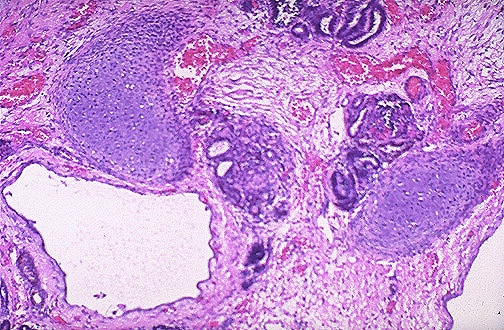

The microscopic appearance of multicystic renal dysplasia is seen here. Note the variably sized cysts and the cartilage.